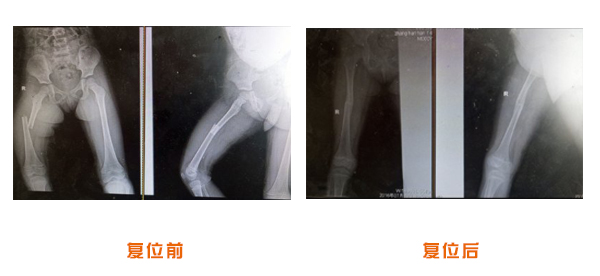

肥城市安駕莊梁氏骨科醫(yī)院是一所以梁氏手法正骨配合膏藥為特色的現(xiàn)代化專科醫(yī)院。

梁氏骨科術始創(chuàng)于清雍正年間,歷經(jīng)八代,至今已有三百年歷史。據(jù)1929年泰安縣志載“梁瑞圖先生,字增生,號蓮峰,安駕莊人,精岐黃并發(fā)明接骨,凡跌打車凡跌打車軋皮不破而碎骨者......【詳細】 |